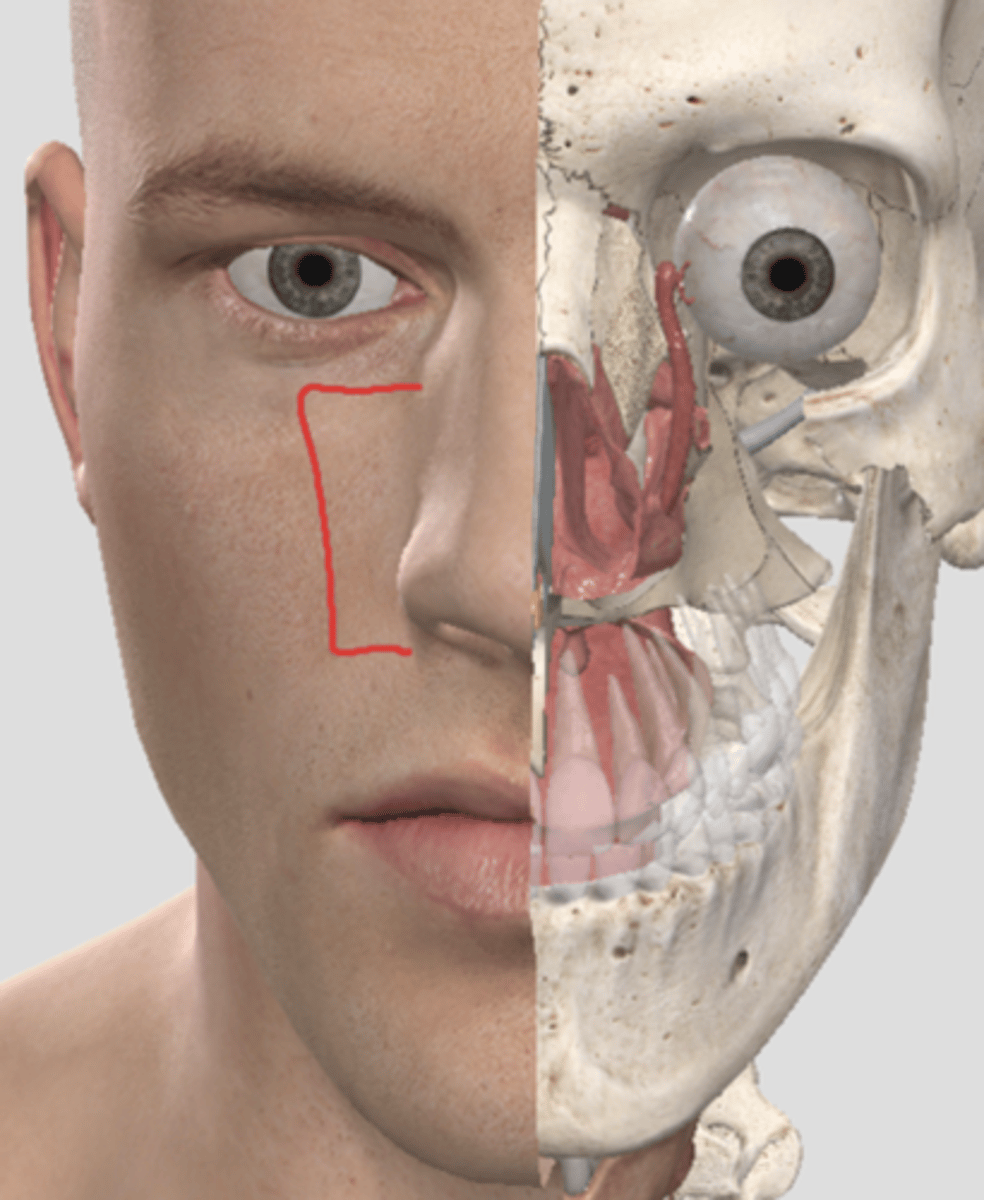

Name A

Name B

Name C

name the circled region

name the circled region

scalene muscles (surface anatomy)

external nares (surface anatomy)

vestibule of the nose (surface anatomy)